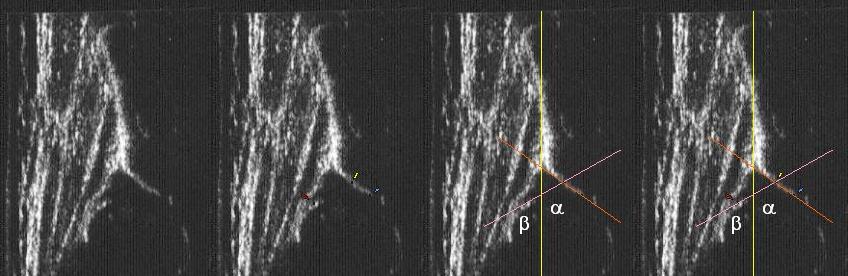

powyżej staw prawidłowy Typ I dach kostny dobry;brzeg kostny tępy ;dach chrzestny pokrywa

dolne zdjęcia

strzałki pokazują obrabek(czerwona):brzeg kostny (żółta);gałąż dolna(niebieska) ,

prawidłowy przebieg linii dachu kostnego(niebieska) stycznie do echa gałęzie dolnej i echa brzegu kostnego ;

linii dachu chrzęstnego (czerwona) stycznie do brzegu kostnego i przez środek geometryczny obrąbka i

linii podstawnej ( żółta

typ I czerwone kropki(od lewej) pokazują punkty do kreślenia 1 środek geometryczny obrąbka 2.brzeg kostny;3.gałąż dolną kości biodrowej

Typ IIc czerwone kropki od lewej) pokazują punkty do kreślenia 1 środek geometryczny obrąbka 2.brzeg kostny(dwa punkty);3.gałąż dolną kości biodrowej